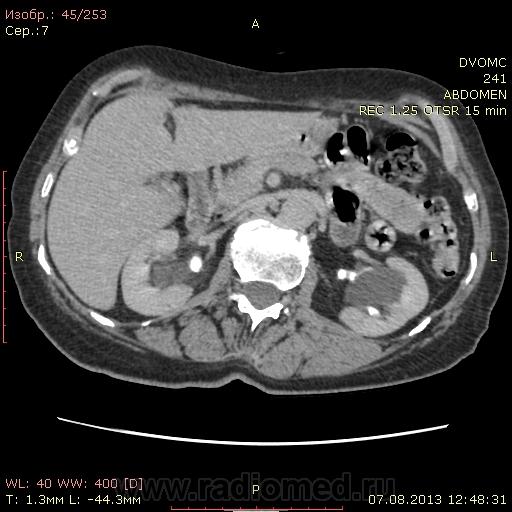

Женщина 73 года. Подскажите, пожалуйста правильно ли я трактую изменения: множественные парапельвикальные и интрапаренхиматозные кисты почек с обеих сторон с деформацией ЧЛС. Перегиб(перетяжка?) желчного пузыря. В остальном - ничего? Еще смутило вот что: контрастное усиление селезенки в артериальной фазе должно быть "пестрым". Всегда до этого пациента было так. Здесь гомогенно усилилась до 135....как это можно расценивать? DICOM файлы http://files.mail.ru/832408BCA4834BBF82010F0764BBDD5A    http://files.mail.ru/422E59E0BACF4E7483F6F9E1FE98ADDF

Да. В большей степени парапельвикальные, чем паренхиматозные.

Перегиб дна.

Билиарный сладж и мелкие конкременты.

Скорее интрапанкреатическая часть холедоха

Похоже на образование правого яичника. Впрочем, в гинекологии предпочтительны УЗИ и МРТ.

Вот, как-то так. Хотя, это может быть и "уехавшая" сюда матка с миоматозным узлом.  Не вижу матки на своем месте. Если удаления не было, возможна она.

Согласна с Андреем Юрьевичем. Только думаю на матку (миома? - УЗИ), а не яичник.